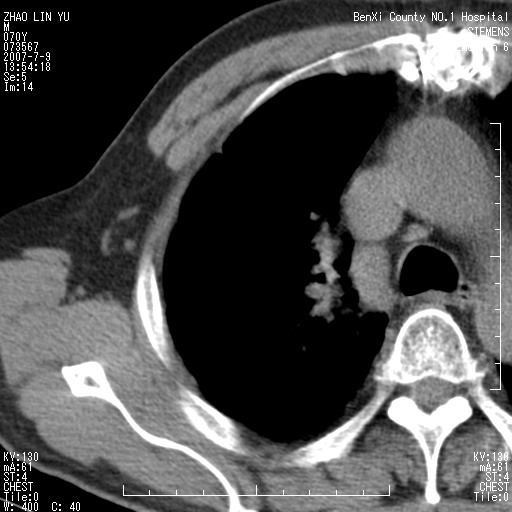

以下是引用王靖旗在2007-7-10 17:12:00的发言:[br] 男、70、咳嗽两个月,半年前换瓣手术,胸片未见异常,于昨天行x片发现右肺上野大片影,行ct扫描,这里是减薄图像,余肺正常。明天晚上会有增强扫描片,到时我会上传。[br][br] 冠状位请大家细看,应该是有意义的,[br][br] 请大家先看平扫发表意见。[br][br]

以下是引用zhangzhongshou在2007-7-10 21:43:00的发言:[br]右肺上叶周围型肺癌,以孤立型细支气管肺泡癌可能性大。